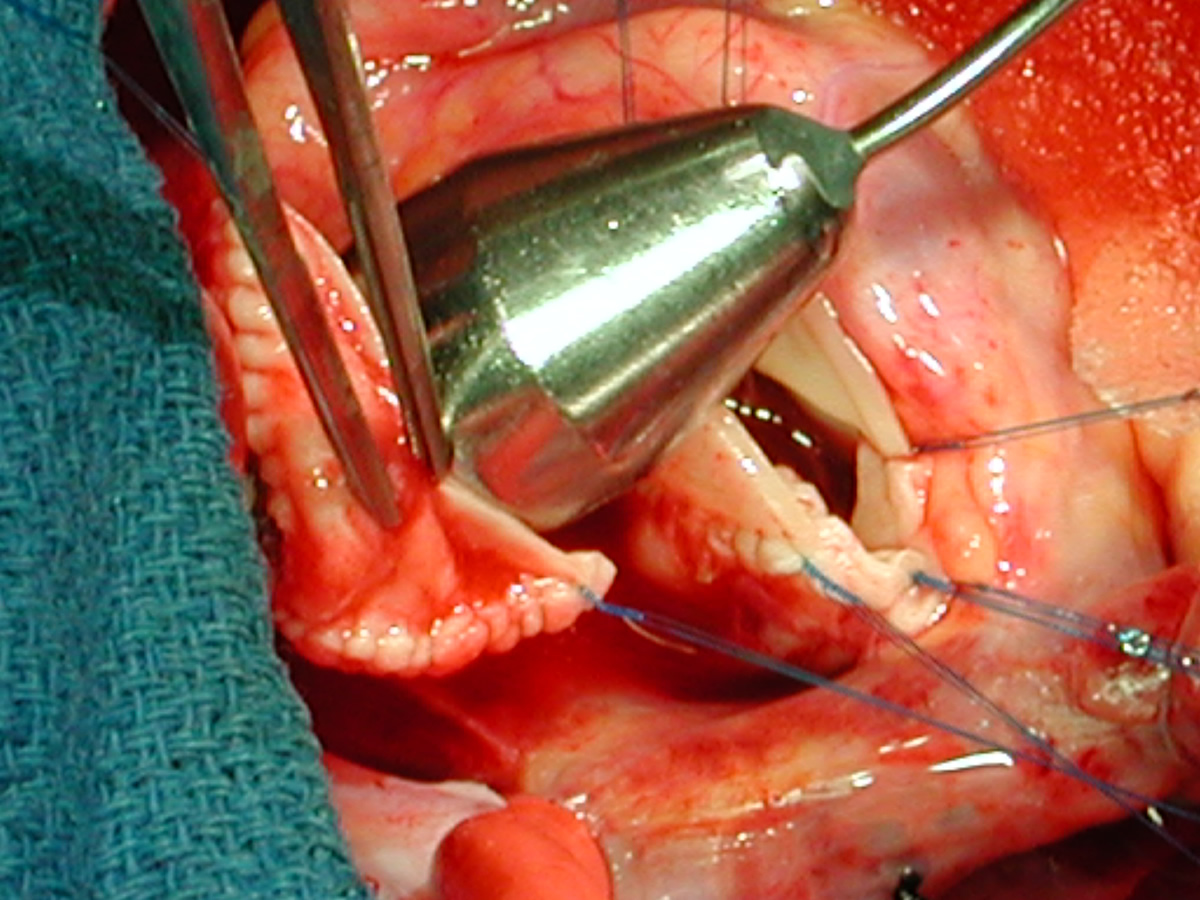

Figures 20 & 21: Third incision has been made to the right of the left coronary orifice. They yellow plastic suture boot on the pickup is pointing out the left coronary orifice. Figures 22 & 23: Proximal ascending aorta now opens widely, revealing the right and left coronary orifices and the normal trileaflet aortic valve below.

Figure Figure Figure Figure